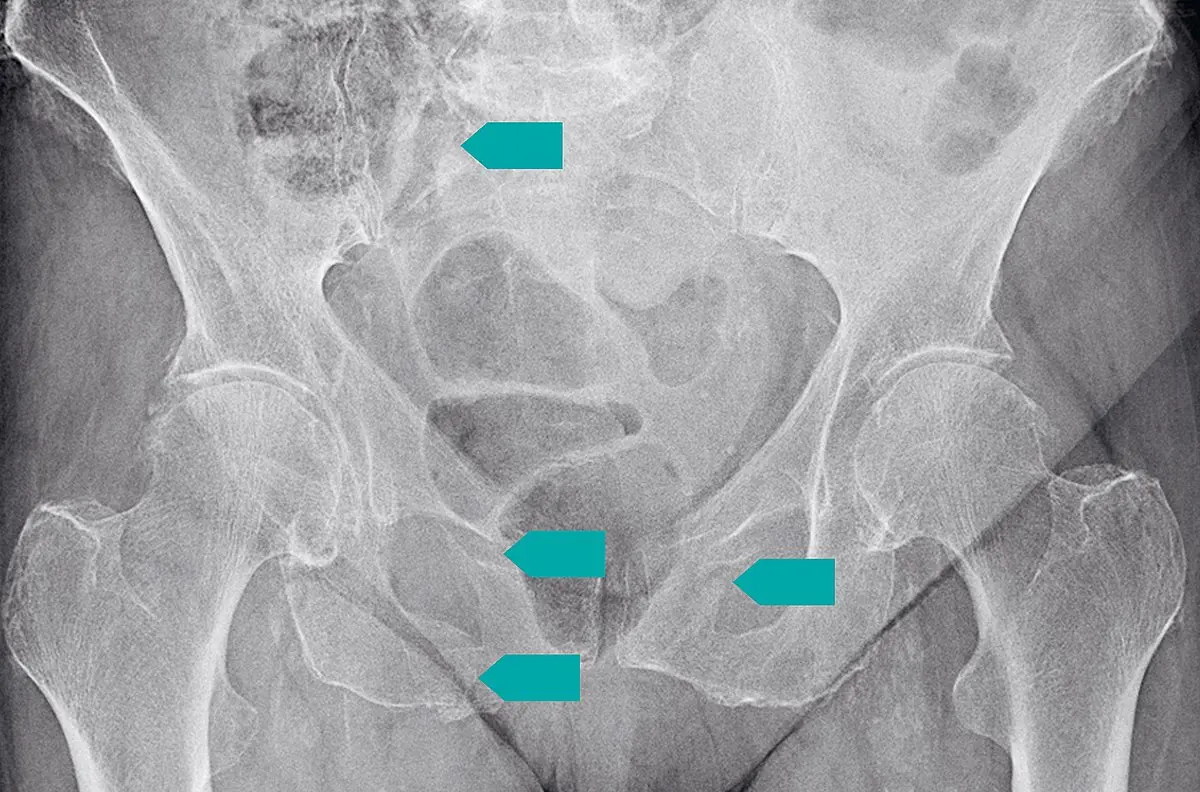

- Röntgenaufnahme : Eine Röntgenaufnahme des Beckens kann einen Kreuzbeinbruch sichtbar machen.

- Computertomographie (CT) : Eine CT-Untersuchung kann detailliertere Bilder des Kreuzbeins liefern und helfen, den Grad der Fraktur zu beurteilen.